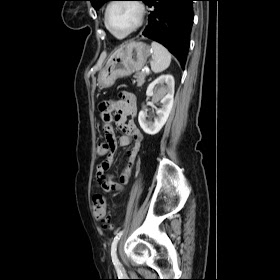

TCC